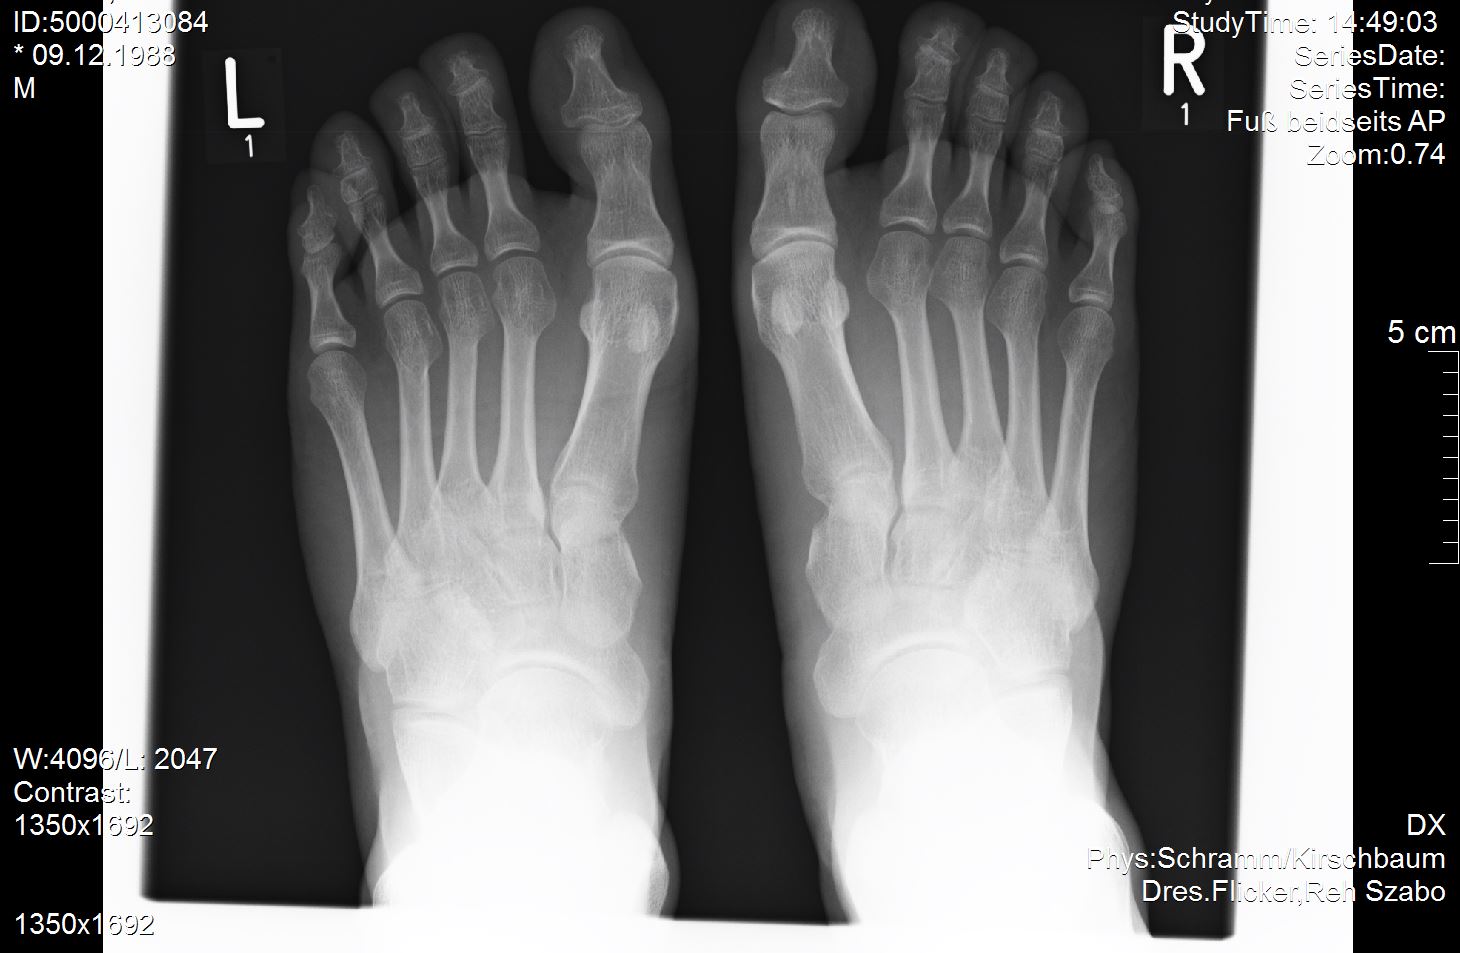

Ich versuche mal meine Röntgenbilder anzuhängen. Vielleicht ist ja ein Experte unter uns der dazu was sagen kann?

Ich habe außer dem mir diagnostizierten Spreizfuß nach oben stehende Zehen. Weiß nicht genau ob man dies Hammerzeh oder Krallenzeh nennt was ich habe aber es geht in die Richtung.